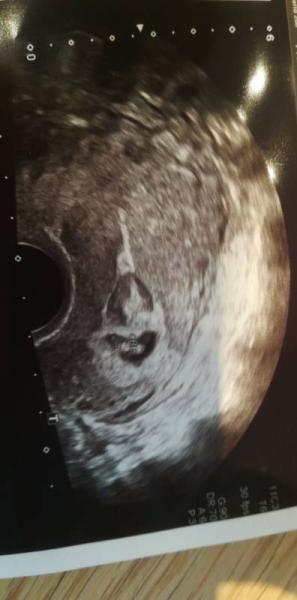

Alles ist gut es lebt und sieht prima aus ich muss mich schonen und habe ab sofort ein Beschäftigungsverbot.. Der ultraschall ging nur 3 Sekunden. Da ich am Dienstag Termin hab für das erste große screening. Danke für die gedrückten Daumen. Er meinte das Blutungen in der ss zu 10% ungefährlich sind.. Anscheinend gehöre ich da dazu

Herzlichen Glückwünsch. Erstmal aufatmen das alles gut ist. Wenn du jetzt nicht mehr die Sorge mit der Arbeit hast geht es dir bestimmt bald besser. Genieß die Ruhe und komm wieder zu Kräften. Vll kannst du ja die Taufe trozdem ein bisschen genießen. Schönes Bild hast du :))